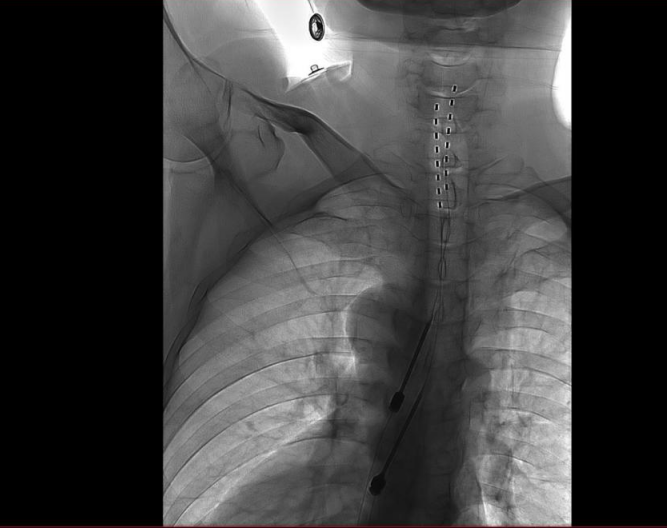

手術(shù)通過微創(chuàng)硬膜外腔穿刺技術(shù),于DSA(數(shù)字血管剪影造影)引導(dǎo)下將極細(xì)的電刺激電極與植入式脈沖發(fā)生器共同植入體內(nèi)。

手術(shù)歷經(jīng)3小時(shí),病人恢復(fù)良好。術(shù)后1周內(nèi),團(tuán)隊(duì)根據(jù)患者疼痛緩解及感覺區(qū)覆蓋情況,對(duì)植入電極的刺激參數(shù)進(jìn)行多次動(dòng)態(tài)調(diào)控,目前廖先生疼痛明顯減輕,預(yù)計(jì)可于近期順利出院。